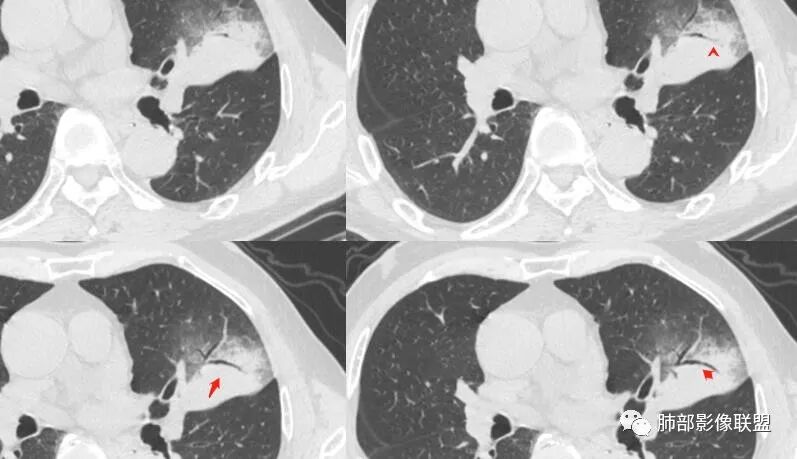

中远端堵塞,堵塞端圆钝

炎性? 肺炎型肺癌待排

这个空洞的性质很重要,对最后诊断结果影响大,如果中间没有曲菌球,那就是偏心空洞,指向恶性,如果是曲菌球引起的新月形改变,那就不一定。至于到底是曲菌球还是偏心空洞,需要仔细看看强化情况。

不均匀性强化,远端坏死比较明显

如果强化明确,那就可以排除曲菌球。

2、偏心空腔病灶,气腔略呈新月形,壁不规则,腔内结节相对密实,明显强化且不均,支持新生物而非曲菌球等。炎性空洞多有强化环。

4、支气管改变:上舌段支气管远段延入部分稍示僵硬。尖后段见分支支气管阻塞,恶性多见。